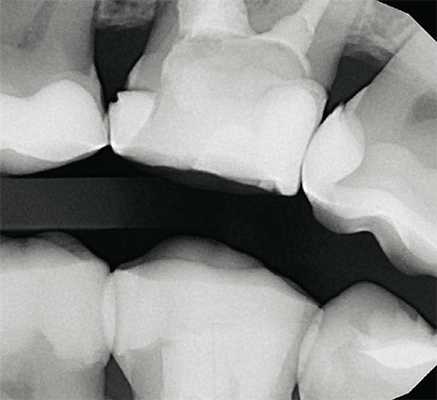

К данному виду исследования относится внутриротовая радиография, выполненная в технике bitewing (рис. 4), и раздельная внутриротовая радиография зуба в ортогональной проекции.

Рис. 4. Интерпроксимальный снимок, выполненный в технике bitewing, исследование состояния контактных пунктов моляров верхней челюсти.

Особенностью интерпроксимальной съемки является, во-первых, то, что приемник изображения располагают в полости рта строго параллельно вертикальной оси и мезиодистальной плоскости исследуемых зубов. Во-вторых, центрация луча (направление центрального пучка луча) проводится либо на линию смыкания зубов (bitewing, рис. 5), либо в прямой проекции на межзубной промежуток строго под прямым углом к вертикальной оси зуба и приемнику изображения, то есть ортогонально.

На снимках, выполненных в bitewing-технике, отображаются коронки исследуемых зубов одновременно верхней и нижней челюсти, пришеечные области, коронковая треть корня и верхний отдел костной ткани межзубной и межкорневой перегородки. Методика предназначена для исследования зубов жевательной группы и неприменима во фронтальном отделе. При ортогональной съемке исследуют зубы только одной челюсти, но во всех отделах. Исследование зубов в ортогональной проекции осуществимо только с использованием позиционирующих устройств. Первый такой позиционер был предложен Хаубериссером еще в 20-х годах двадцатого столетия и мог быть легко изготовлен из проволоки и пробки (рис. 6).